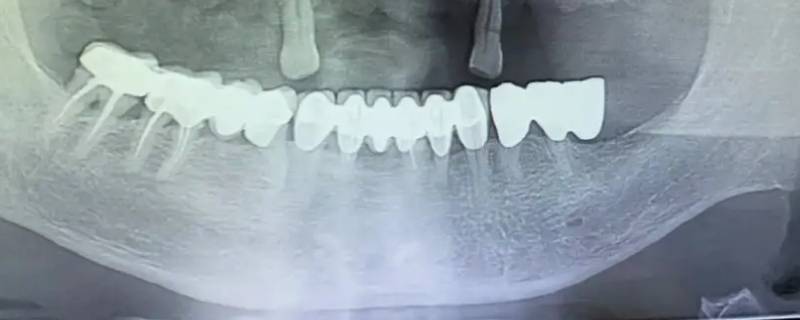

最佳答案在全景片显影中,骨骼、牙齿、补牙材料、牙冠这种组织属于高密度组织,在影像上呈现白色;像牙龈和牙髓这一类组织属于低密度组织,低厚度组织,会呈黑色或灰色。蛀牙在全景片显影上会出现黑色阴影的缺损,如果是邻面龋以及龋坏程度,通常需要到医院,医生用探针、口镜等进行确定。

在全景片显影中,骨骼、牙齿、补牙材料、牙冠这种组织属于高密度组织,在影像上呈现白色;像牙龈和牙髓这一类组织属于低密度组织,低厚度组织,会呈黑色或灰色。蛀牙在全景片显影上会出现黑色阴影的缺损,如果是邻面龋以及龋坏程度,通常需要到医院,医生用探针、口镜等进行确定。